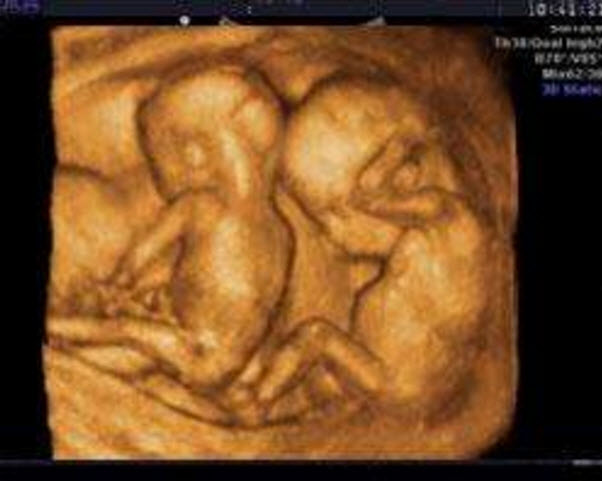

超聲波檢查檢測到兩個胎心波

超聲波檢查檢測到兩個胎心波是最明顯的懷雙胞胎的癥狀。如果懷了雙胞胎,那么用超聲波檢查就可測到兩個不同速度的胎心波,同時用X線檢查也會顯示兩個胎兒的骨骼。